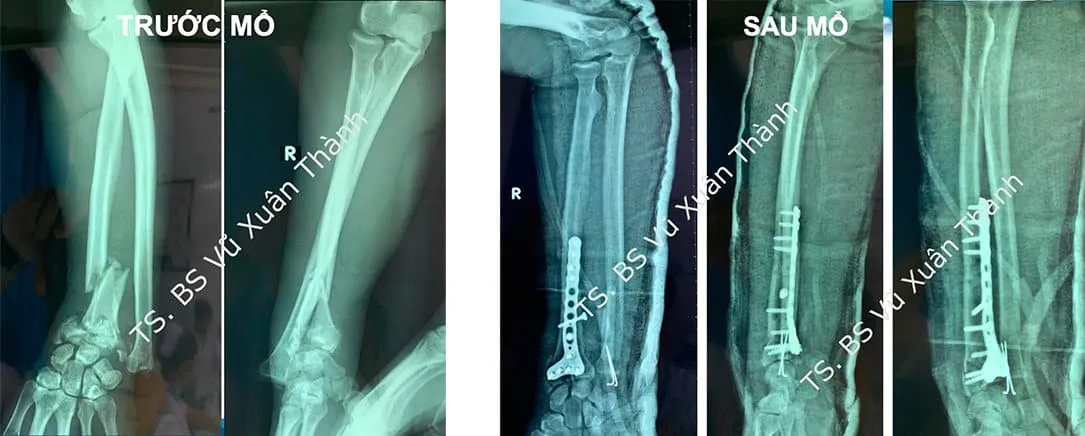

Điều trị gãy xương bằng cách mổ hở và cố định trong

Mổ hở và cố định trong có thể được thực hiện nếu bệnh nhân bị gãy xương ở nhiều vị trí, ổ gãy không vững hoặc di lệch, có tổn thương các dây chằng xung quanh, các mảnh xương gãy có nguy cơ gây tổn thương khớp…

Trong phẫu thuật này, bác sĩ sẽ nắn các mảnh xương gãy về đúng vị trí ban đầu và sau đó giữ chúng kết nối với nhau bằng các loại ốc vít đặc biệt hoặc các tấm kim loại ở bề mặt ngoài xương. Bác sĩ cũng có thể cố định các mảnh vỡ bằng cách đặt một thanh kim loại vào lòng ống tủy xương.